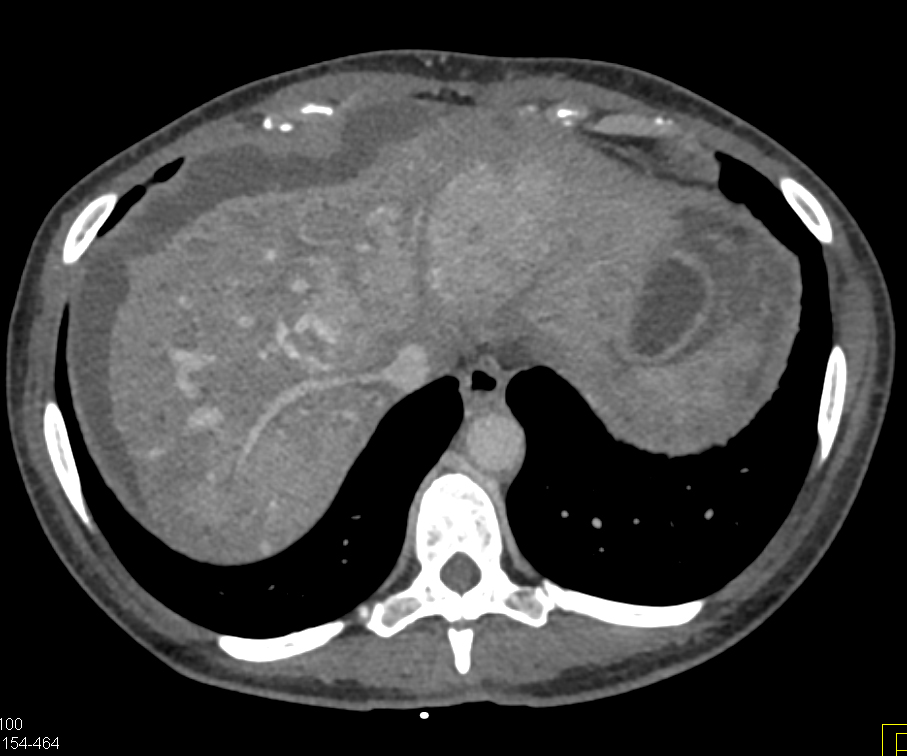

Diagnostic Case Quiz ❯ Anatomical Region Quiz: Liver

The best diagnosis in this case is?

hepatoma

cirrhosis

regenerating nodules

liver metastases